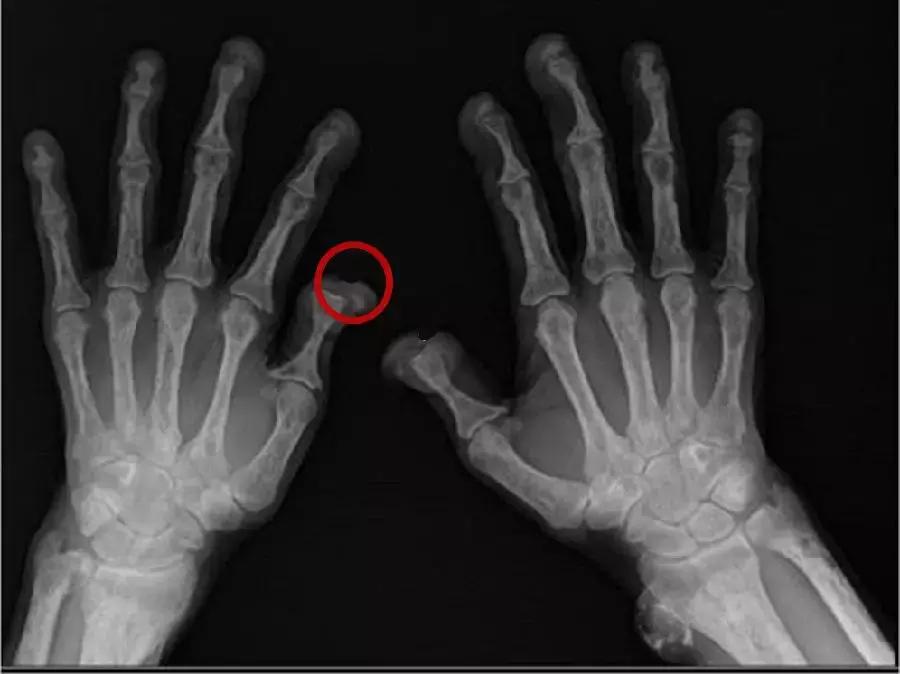

X线很清楚的显示,他的手指骨头出现了“溶解”样的改变,特别是两只手的大拇指,大拇指远端关节几乎完全溶解了。

对比正常的手部X线,大家能明显看出区别,左边是这位患者的,右边是正常人。